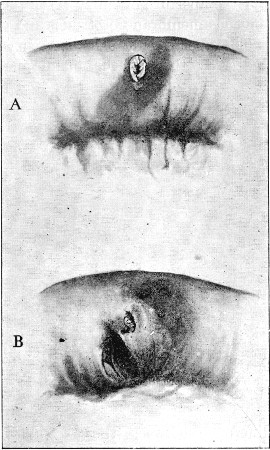

16. Entry and Exit Mauser Wounds56

17. Gutter Wound of Shoulder56

18. Oblique Gutter Exit Wound 57

19. Oval Entry, Starred Exit Wounds58

20. Circular Entry, Slit Exit Wounds59

21. Circular Entry, Starred Exit Wounds59